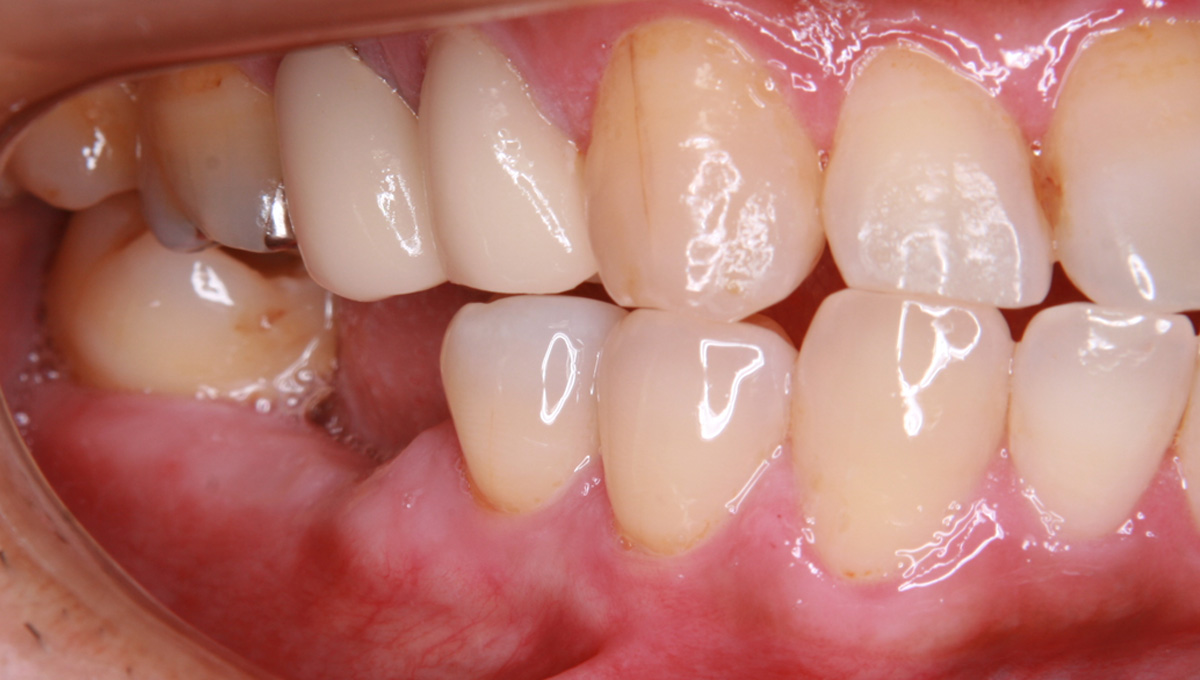

抜歯した箇所にインプラント治療を行った例

術前・術後の比較

初診時

歯が割れていて、痛みがあり、抜歯となりました。

パノラマレントゲン写真 -

インプラント手術から3ヵ月後、型どりをして、仮歯を製作しました。

仮歯の調整期間を経て、セラミックの歯が入りました。

レントゲン画像 治療前 インプラント治療後